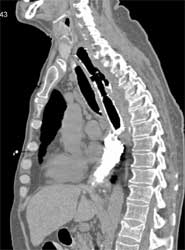

Nodes From Esophageal Cancer